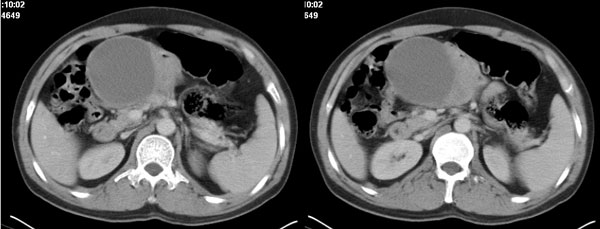

李**,男,46岁,便血1天入院,慢性贫血貌,腹平、软,剑突下压痛,肠鸣音稍活跃,hb大于1g/l,胃镜:慢性浅表性胃炎,b超:1肝内多发性占位 2腹腔内囊性肿块 ,肝内圆形影平扫ct值42.9,动脉期48.6,静脉期58.2,延迟期62.2

影像学表现:1 腹腔前中部、胰腺前方囊实性病灶(个人认为确定有否实性成分存在这是关键,涉及到鉴别诊断,如果是口服阳性造影剂则可明确左侧是不是小肠了),囊性部分囊壁不均,实性部分有强化,与小肠关系较密切,局部小肠受推移;与胰头、胃后壁均有脂肪间隙存在;2 胰腺无异常改变,胰周无渗出;3肝后段包膜下2个小圆形低密度灶,从图像和楼主提供的ct值来看有轻度强化,灶周无片状强化,不似单纯囊肿及肝癌、炎性病变表现;4 腹膜后及腹腔内无淋巴结肿大。

胰腺边界清晰,胰周筋膜不厚,胰周脂肪密度无明显增高;其前方囊实性病灶,边界清晰,增强后实性部分轻度强化;肝内多发边界清晰低密度影,增强后无明显强化(平扫ct值42.9,动脉期48.6,静脉期58.2,延迟期62.2)。